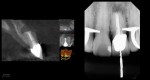

This was interesting because a root frac ture was seen where the prior apico was done. The MTAS was removed and Brassler putty used in this case. Will take a 1 yr CBCT and we will know more. Don’t usually get so much scar formation–so this was surprising…..